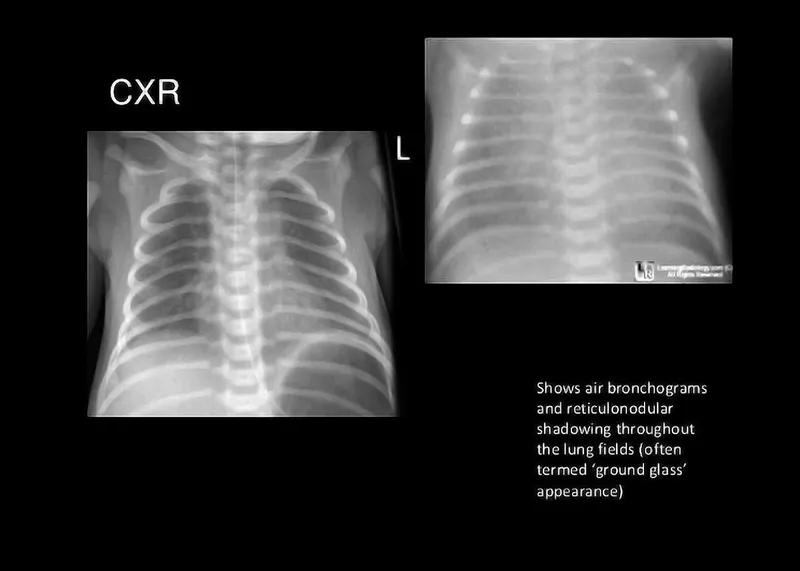

- Respiratory Distress Syndrome (RDS): Surfactant deficiency in preterms (<34 weeks).

- CXR: Ground-glass, air bronchograms.

- Rx: Antenatal steroids, surfactant, CPAP.